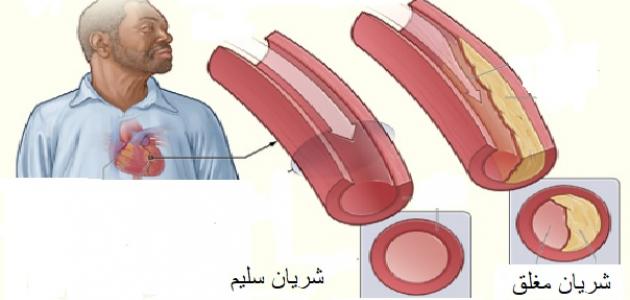

تحدث الإصابة بأمراض الشريان التاجي والأوعية الدموية نتيجة المعاناة من تصلّب الشرايين (بالإنجليزية: Atherosclerosis) في الغالب، ويُعدّ داء الشريان التاجيّ أكثر أنواع أمراض القلب شيوعاً، وهو المسبّب الرئيسيّ للنوبات القلبيّة والذبحة الصدريّة (بالإنجليزية: Angina)، إذ يكون مصحوباً بتضيّق أو انسداد الشرايين التاجيّة المغذية لعضلة القلب، أمّا بالنسبة لأمراض الأوعية الدمويّة ذات الصلة فهي الأمراض التي تصيب أنواع أخرى من الشرايين والأوردة وتؤدي إلى ضعف التروية الدمويّة وتؤثر في وظائف القلب.[٣]

تحدث الإصابة بالنوبة القلبيّة أو ما يُعرَف أيضاً باحتشاء عضلة القلب (بالإنجليزية: Myocardial infarction) نتيجة الانخفاض الشديد في سرعة تدفّق الدم في أحد الشرايين التاجيّة المغذية لعضلة القلب، أو انسداده بشكلٍ مفاجئ، وفي الغالب تكون الإصابة بالنوبة القلبيّة ناجمة عن تشكّل الخثرة الدمويّة في أحد الشرايين التاجيّة المتضيّقة نتيجة المعاناة من تصلّب الشرايين.[٧]

وفي هذا السياق يُشار إلى أنّ تصلّب الشرايين هو التضيّق والتصلّب الحاصل في الشرايين نتيجة تراكم الدهون التي تُسمى الصفيحات الدهنيّة في جدرانها، ممّا يؤدي إلى إعاقة تدفّق الدم خلالها وضعف التروية الدمويّة للعضو المُغذّى بهذا الشريان، بالإضافة إلى ارتفاع خطر تشكّل الخثرات الدمويّة التي قد تؤدي بدورها إلى انسداد الشريان، وقد يكون الشريان مسؤولًا عن تغذية الدماغ أو القلب، ويشار إلى أنّ مرض تصلّب الشرايين قد لا يكون مصحوباً بأيّة أعراض واضحة، ممّا يؤدي إلى تطوّر المرض دون علم الشخص المصاب، وقد يؤدي إلى المعاناة من بعض المضاعفات الصحيّة الخطيرة في المراحل المتقدّمة من المرض مثل الجلطة الدماغيّة والنوبة القلبيّة، وتجدر الإشارة إلى إمكانيّة الحدّ من خطر الإصابة بمرض تصلّب الشرايين بشكلٍ كبير من خلال اتّباع أسلوب حياة صحيّ، والوقاية من تطوّر المضاعفات الصحيّة في حال حدوثه من خلال الالتزام بالخطة العلاجيّة التي يصفها الطبيب.[٨]